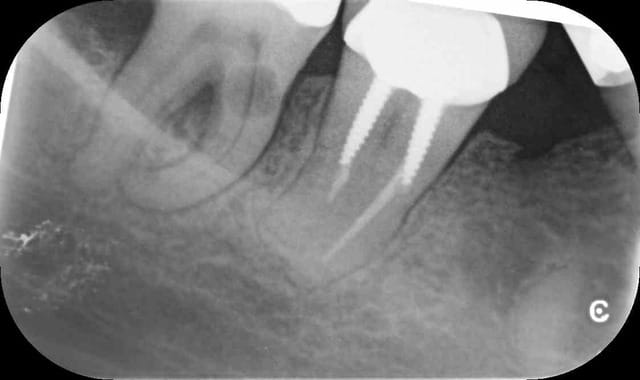

C'est une image typique de résorption externe, ci joint un cas récent d'un confrère qui me demandait mon avis également sur le même type de lésion, il m'a transmis la photo de la dent après l'extraction. La décision d'extraire a été prise car une atteinte osseuse de la furcation commençait. La dent était elle complètement asymptomatique et répondait tout à fait normalement au test de vitalité, car la résorption externe préserve en général le tissus pulpaire

--